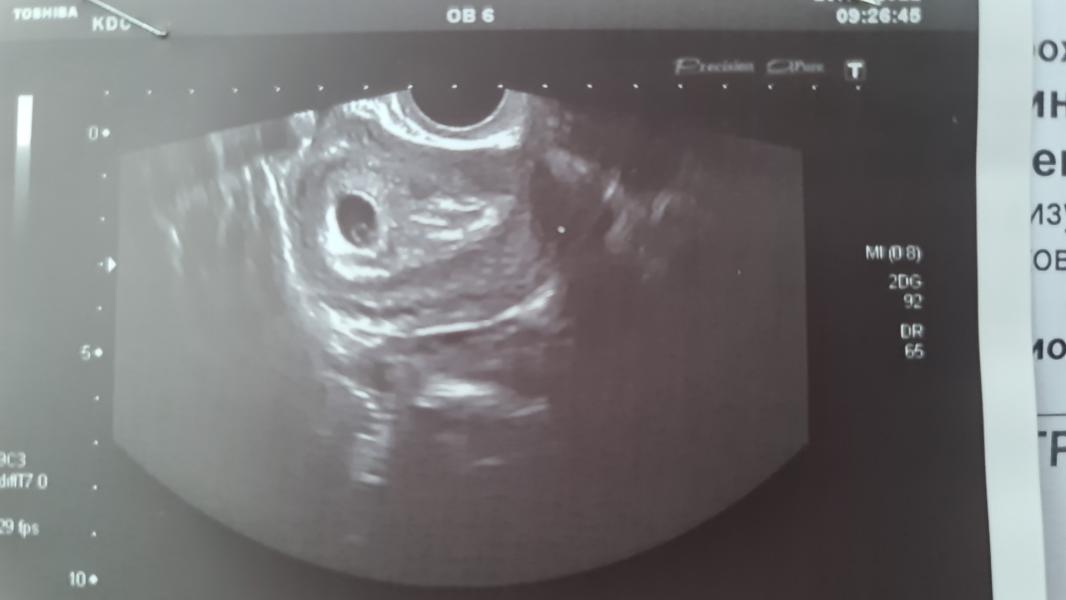

Я ложусь,он вставляет датчик с абсолютно спокойным настроем и тут он такой😱😱😱"Анастасия, вы что в себя поверили?вы как-то жёстко занимались сексом?африканские страсти?" И смеется сквозь шок и удивление во взгляде) мы начинаем ржать,я отшучиваюсь тоже,тут он зовет коллегу и медсестру и показывает картинку и говорит:"Вы знаете,то что я вижу не имеет ни медицинского,ни физиологического объяснения!я не знаю как это получилось,это можно считать чудом..или волшебством..". Ну и разворачивает экран ко мне и показывает, как матка разделилась ровно на 2 половины и в одной есть плодное яйцо,там эмбриончик и бьется сердечко(это уже видно,но не слышно),а с другой стороны грубейшие спайки и неоднородный эндометрий.В итоге он разрешил записать микро видео,где видно как качает сердечко и скзаал:"я сам тоже запишу видео,отправлю всем в институте,это просто капец ,я слов подобрать не могу и сейчас побегу к профессорам". Скзаал,чтоб я пришла через неделю еще раз,чтоб посмотреть как там развивается всё. ПО месячным было вчера 6.1 недель,а по плодному яйцу 5.5 недель,я думала что будет больше отставание,но нет,я рада))2 декабря увидимся снова.. и вот я опять переживаю,что же дальше будет с моей крошкой(((не помешает ли это всё развитию...слева плодное яйцо,а справа это все спайки,все эти неровности